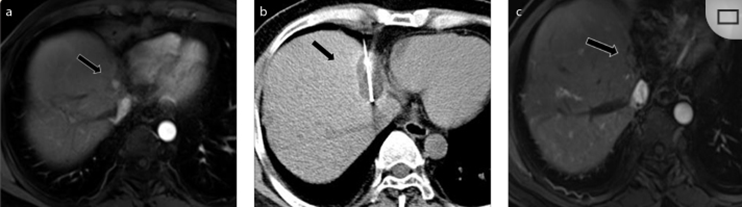

79 歲男性,肝轉(zhuǎn)移(結(jié)直腸癌)腫瘤的完全消融病例

( a ) 軸向 MRI 和 ( b ) 軸向 CT 顯示肝S8段有一個(gè)16mm的病灶,鄰近肝緣。( c )冷凍消融期間CT顯示放置了2個(gè)冷凍探針,低密度冰球包圍病灶。(d)術(shù)后1個(gè)月隨訪 CT顯示冰球?qū)?yīng)的壞死區(qū)域,未見復(fù)發(fā)。(e)術(shù)后6個(gè)月的CT,壞死區(qū)域縮小,未見復(fù)發(fā)。(f)與基線影像(g)相比,12個(gè)月后的FDG-PET/CT顯示未見FDG攝取。

62歲女性,肝轉(zhuǎn)移(卵巢癌)腫瘤的完全消融病例(a)軸向CT顯示病變位置毗鄰心臟和上腔靜脈(黑色箭頭)。(b)術(shù)中軸向CT掃描:使用三個(gè)冷凍探針。1個(gè)月后的軸向(e)和冠狀位(f)增強(qiáng)CT掃描顯示低密度區(qū)域,由于肉芽組織反應(yīng)引起的邊緣增強(qiáng)。

技術(shù)成功100%,92% 的病灶中觀察到腫瘤完全消融。16 名患者 (33%) 出現(xiàn)局部復(fù)發(fā)。10 名患者 (20%) 因局部復(fù)發(fā)或腫瘤消融不完全而接受二次冷凍消融術(shù)。

7名患者出現(xiàn)輕微并發(fā)癥,未發(fā)現(xiàn)膿腫形成、膽漏、膽汁瘤或血液學(xué)變化。冷凍消融可安全、有效治療毗鄰重要臟器的原發(fā)性肝臟腫瘤和肝轉(zhuǎn)移瘤患者,有效控制腫瘤局部進(jìn)展,使患者生存獲益。我國(guó)作為肝癌大國(guó),對(duì)于肝癌的治療一直給予高度重視。基于專家共識(shí)和相關(guān)文獻(xiàn)研究結(jié)果顯示,冷凍消融技術(shù)具有高效、低成本、創(chuàng)傷小、適應(yīng)證廣、并發(fā)癥相對(duì)較少等優(yōu)點(diǎn),可有效延長(zhǎng)患者生存期、提高生活質(zhì)量、降低患者經(jīng)濟(jì)負(fù)擔(dān)。因此,冷凍消融技術(shù)在肝癌的應(yīng)用中有著極高的潛力和廣泛的發(fā)展空間。